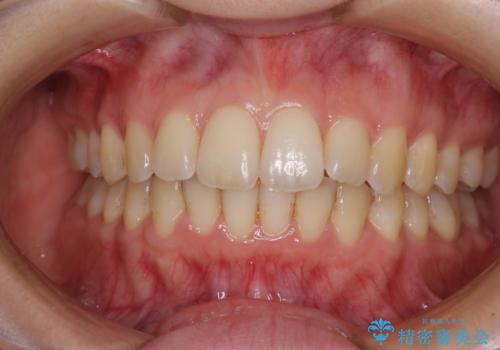

- デコボコした前歯をセラミックできれいに揃えたいとのことで来院された患者様です。

歯を削って整えることは簡単ですが、健全な歯を削って後悔してからでは遅いため、矯正治療を提案しました。

はじめは矯正治療の期間が長いことに悩んでいらっしゃいましたが、ある程度整えば満足するだろうとのことで、インビザラインにて矯正治療を行うこととしました。

インビザライン矯正は、1日22時間を目安に装着する必要がありますが、しっかりと装着してくださったので、順調に治療を進めることができました。